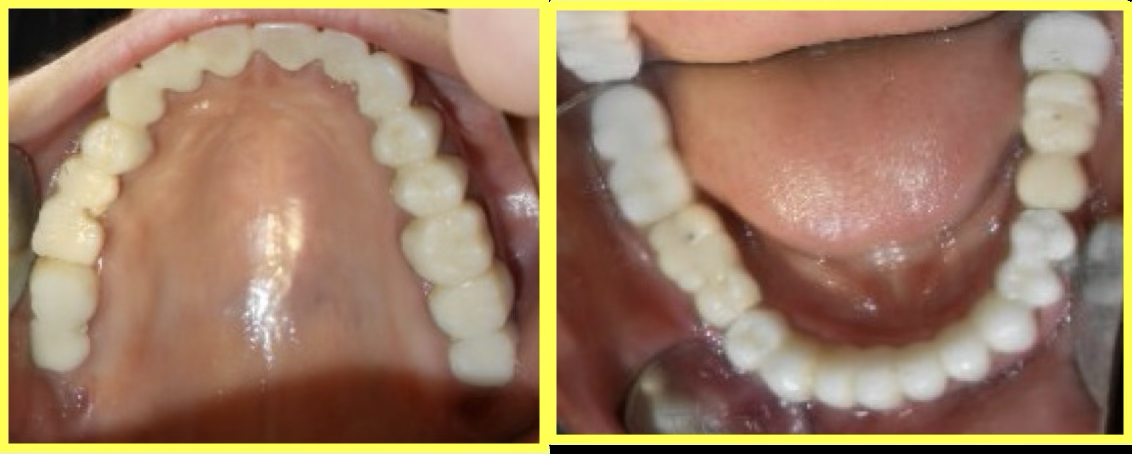

Final result

A 57-year-old female patient visited our dental center complaining of multiple missing and attrited teeth. On examination, patient had missing teeth 25, 26, 35, 36, 45 & 46 with grade 3 attrition. Treatment included impression-based muscle deprogrammer, Dio implants placement, PFM crowns for remaining attrited teeth, and delayed implant loading after 3 months.

Permanent Porcelain Fused to Metal (PFM) crowns were custom-fabricated and cemented. Implants were delayed loaded after 3 months of healing.